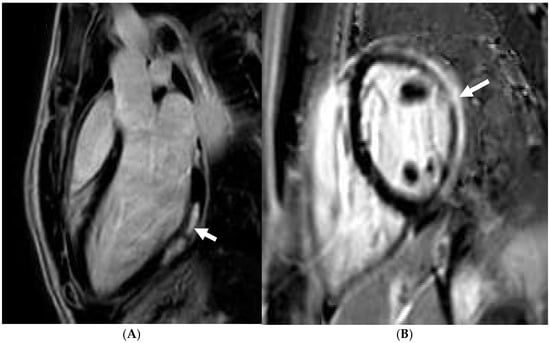

Tissue characterisation with cardiac MRI also plays a key role in athletes with a suspicion of HCM. Post-contrast imaging with late-gadolinium enhancement (LGE) is used to detect macroscopic replacement fibrosis (Figure 3). The presence of fibrosis is diagnostic of a disease process, often patchy and present in hypertrophied segments. Extensive LGE has also been associated with an increased risk of ventricular arrhythmias and SCD [67,68,69]. LGE is, however, only present in 60% of HCM cases [68,70], implying that the absence of fibrosis should not preclude labelling an athlete with HCM. T1 mapping has an important role in LGE-negative HCM cases. Myocyte hypertrophy, rather than expansion of the extracellular matrix, often leads to lower T1 values, especially in endurance and male athletes. This provides a valuable insight into the pathophysiological process of athletes with LV hypertrophy [71,72,73]. Pathological LVH, on the other hand, is positively correlated with ECV, suggesting that an increase in the extracellular matrix is the main contributing factor towards an elevated LV mass [74]. T1 mapping certainly holds promise, yet it requires extensive validation in large athletic cohorts with HCM. LGE and mapping sequences may also play a diagnostic role in HCM phenocopies when cardiomyopathy coincides with extracardiac manifestations. There is a typical abnormal post-contrast myocardial nulling in cardiac amyloidosis. T1 values are, conversely, significantly reduced in Fabry’s disease [75].

Figure 3. Caucasian male soccer player presenting with inferolateral T-wave inversion on ECG. SSFP cine imaging (A) showing apical hypertrophy, with evidence of apical fibrosis on post-contrast imaging (B,C).